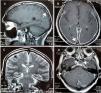

After two weeks, he began presenting progressive involvement of the III and VI cranial nerves and purulent nasal discharge was present. Gadolinim-enhaced brain MRI was performed showing fluid in mastoid air cells, right middle ear and left sphenoid sinus. In addition, it showed dura mater thickening and an increased contrast uptake in the pachymeninges in botch cerebral convexity and cerebellar tentorium (Fig. 1), these findings were compatible with diffuse hypertrophic pachymeningitis, left sphenoid sinusitis and right chronic otomastoiditis. No relevant findings were found in thoracoabdominal CT. At that time, several laboratory tests were performed in order to reach the underlying etiological diagnosis of the HP (Table 3).

(A) Pachymeningeal thickening in non-contrast MRI (B and C) Diffuse enhancement dural thickening in cerebral convexity and cerebellar tentorium consistent with pachymeninigitis in T1- and T2-weighted MRI (arrows). (D) Axial MRI shows right otomastoiditis and left sphenoid sinusitis (arrows).